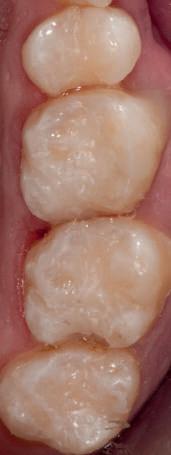

HYBRID COMBINATION RESTAURATIONS

Vonlay-uri: o alternativă conservatoare estetică la coroanele cu acoperire totală